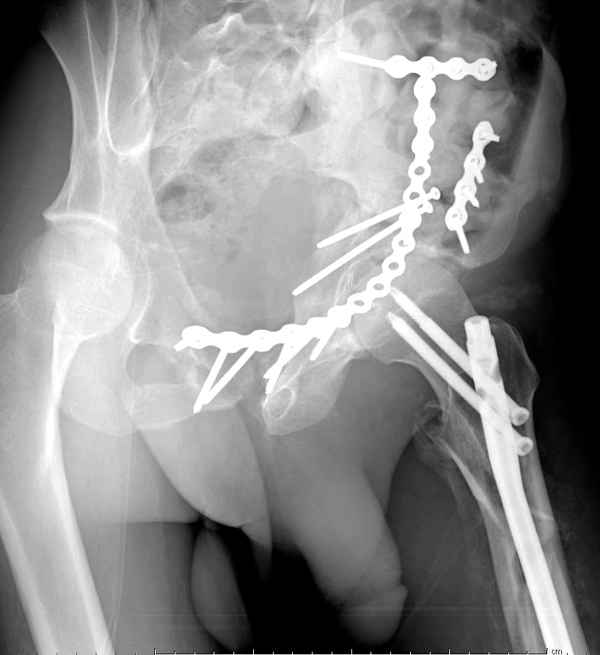

ключевой момент в подобной ситуации если думать о реконструкции под эндопротез - репозиция задней колонны. Что сделать сейчас - нужно начать со стандартных проекций Judet. Исправить ситуацию сейчас очень сложно и рискованно.

итак, второй вариант: высокий двухколонный с вовлечением КПС... Ни одно из основных повреждений не репонировано, кроме задней стенки. Скорее всего попытка реконструкции вертлуги сейчас будет очень травматичной и не очень эфективной, т.е. вероятный риск более значим, чем ожидаемая польза... Лучше подождать, и потом сразу эндопротез

>Лучше подождать, и потом сразу эндопротез

подождать сколько, чего? такая дыра в задней колонне не закроется никогда.

потом эндопротез какой? в такой ситуации приходит на ум Burch-Schneider cage, в 35 лет, дальше что делать?

Когда перелом не получается отнести к какому либо типу - эффективнее всего описать более детально. В дальнейшем проще бывает сортировать, и что важнее - "руководство к действию" бывает более обоснованным. В данном случае графа клинического диагноза может выглядеть так: Застарелый разрыв правого крестцово-подвздошного сочленения, консолидирующиеся со смещением переломы крыла и тела правой подвздошной кости, обеих колонн и задней гемисферы правой вертлужной впадины. Состояние после остеосинтеза.

Исходя из возраста пациента без сомнения желательно подготовить основу для установки "Press Fit" (Magnum). Одним словом сначала необходимо выполнить Реконструкцию.

>Застарелый разрыв правого крестцово-подвздошного сочленения, консолидирующиеся со смещением переломы крыла и тела правой подвздошной кости, обеих колонн и задней гемисферы правой вертлужной впадины. Состояние после остеосинтеза.

исходя из непонимания паттерна повреждения, как вы собираетесь подготовить впадину? Доступы? сразу протез или реконструкцию или создание bone stock? secondary congruency?

А что Ввам не понятно? И что Вам дадут нового в понимании паттерна данного повреждения "стандартные проекции"? Согласен! Есть детали, которые требуют осмотра пациента, но это детали. А тактика, как уже и говорилось: Реконструкция, потом эндопротезирование. Доступ... Впрочем, нагляднее посмотреть презентацию (прикрепленный файл). В представленном случае все делалось одномоментно - реконструкция и эндопротезирование. Доступы сочетались (задний и подвздошно-паховый). В данном же случае желательно выполнить в 2 этапа.

понимание Классификации Летурнеля позволило бы вам скорее всего выполнить реконструкцию под эндопротез из одного стандартного доступа в одну сессию, а не из двух с непонятным отпиливанием крыльев. Два доступа имели бы смысл, если бы планировалась полная реконструкция сустава в расчете на его функционирование его какое-то время. Представленный вами случай задает больше вопросов, чем ответов. Стоило затевать такую реконструкцию, чтоб установить обычную цементную чашку. Зачем 2 этапа для первичного эндопротезирования?

Из какого одного "стандартного" доступа вы собираетесь выполнить реконструкцию спустя 3 месяца? Из расширенного подвздошно-бедренного или У-образного с flip остеотомией большого вертела. В обеих случаях, скорее всего, разрез будет в проекции послеоперационного рубца. А мы даже пациента не видели. А задние отделы?!!! Надо фиксировать или нет? А если надо, то как, каким доступом? У "непонятного" отпиливания крыла - есть вполне понятные причины и обоснование. Это не ново! Или перкутанно фиксировать КПС? (спустя 3 месяца)!

А почему в 2 этапа? Исключительно для установки press-fit, а не обычную цементную чашку в реконструированную первым этапом и сросшуюся вертлужную впадину.

По-моему, надо готовить больного к будущей артропластике, но без опоры на задний столб невозможно удержать протез. Опорная конструкция (кольца и т.д.) должны иметь опору, и поэтому мы бы сделали реостеосинтез задним доступом. При надобности остеотомия и рутинная фиксация с межколонными винтами.

Здесь несколько вариантов двухколонных свежих переломов, которые были оперированы из одного-заднего, а также из двух: переднего и заднего доступов.